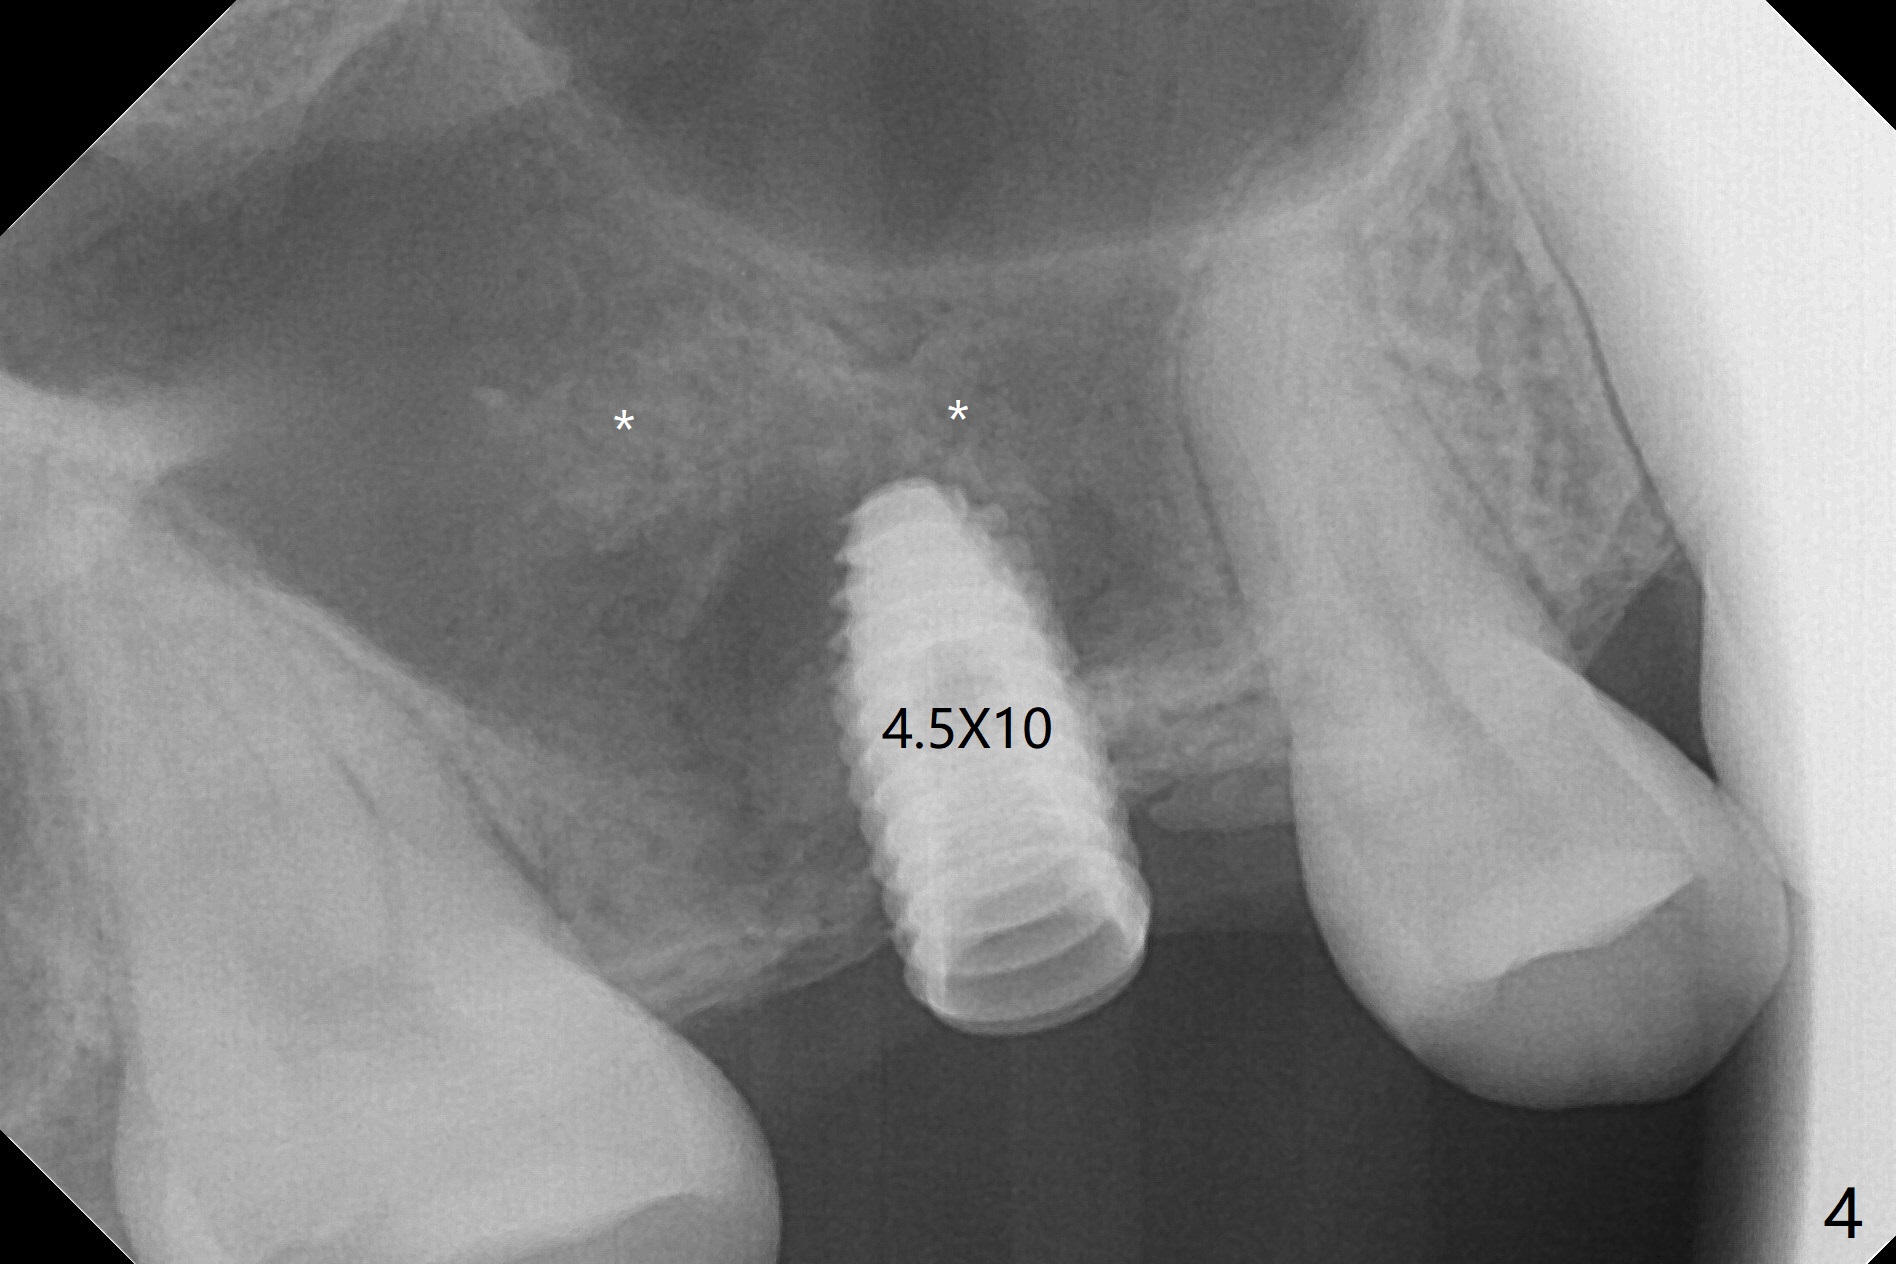

When the residual roots of the tooth #3 are removed, there is a gingival band over the septum (Fig.1 S). Osteotomy (Fig.2 yellow circle) would tear it off. To save the soft tissue, the buccal attachment is severed (Fig.3 black line), the flap is rotated palatal (Fig.3 curved arrow) and sutured in place (Fig.5 S). After sinus floor breakdown (use of sinus drill for 16 mm) and use of membrane lifter/water, two pieces of PRF membrane are inserted. The membrane is so slippery that it is easy to enter the sinus for further sinus membrane lift and later allograft placement (Fig.4 *). A 4.5x10 mm dummy implant is placed with high torque after 4x7.3 mm drill with 3 mm stopper so that 4.5x7.3 mm drill with 1 mm stopper is used before placement of a 5x8.5 mm final implant with ~ 35 Ncm (Fig.5-7). The patient reports anterior sinus wall tenderness with right nasal discharge a few days postop. The provisional has mobility without tenderness 1 week postop. It appears that the sinus membrane has been involved, which is quickly repaired probably by PRF. There is no pain when a 5.2x4(2) mm cemented abutment is torqued at 30-35 Ncm before impression (Fig.8). The surrounding soft tissue is healthy. When the permanent crown is delivered, the patient feels light pain when she bites hard. The discomfort persists 4 months post cementation (Fig.9). The crown/abutment is replaced with a healing abutment (Fig.10). There is no bone loss 4 months post healing abutment placement (14 months post implant placement, Fig.11). Upper Molar Immediate Implant, Prevent Molar Periimplantitis (Protocols, Table), Trajectory II, 31 Flap Not Transferred Xin Wei, DDS, PhD, MS 1st edition 07/26/2019, last revision 10/05/2020